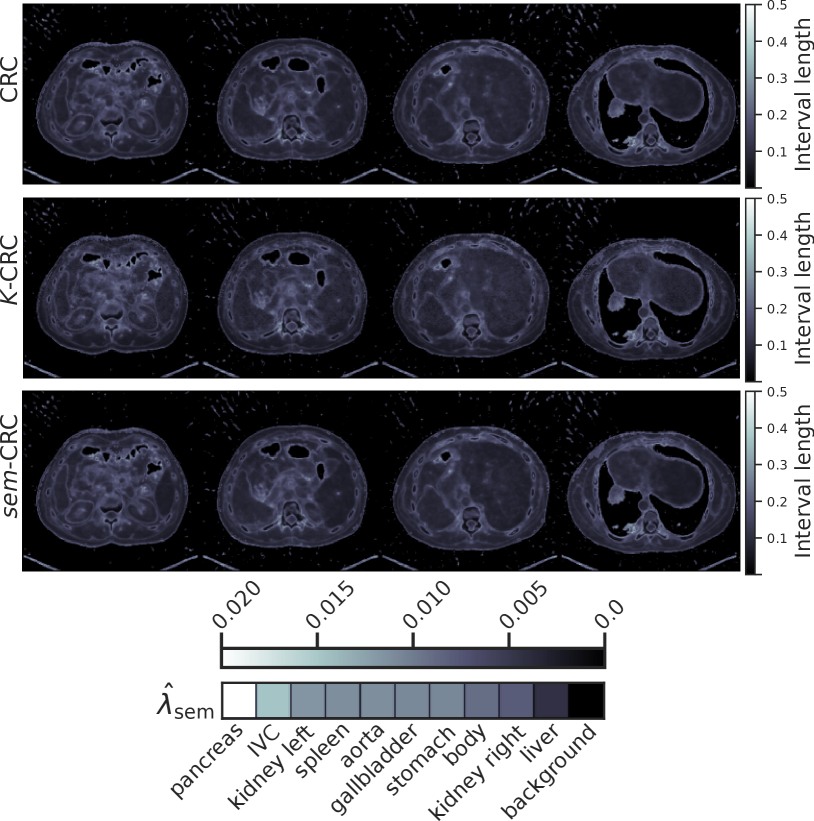

Refer to caption

(a) TotalSegmentator.

(b) FLARE23.

Figure 2: Example conformalized uncertainty maps on one volume per dataset with each calibration method for the FBP-UNet pipeline. The bottom row shows 𝝀^semsubscript^𝝀sem{\hat{\bm{\lambda}}}_{{\text{sem}}}over^ start_ARG bold_italic_λ end_ARG start_POSTSUBSCRIPT sem end_POSTSUBSCRIPT, the semantic uncertainty parameter learned by our method, sem-CRC𝑠𝑒𝑚-CRC{sem\text{-}{\text{CRC}}}italic_s italic_e italic_m - roman_CRC.

Table 1 summarizes risk and mean interval length across all datasets and tasks. All procedures are valid, i.e. they control risk at level ϵitalic-ϵ\epsilonitalic_ϵ. Our method, sem-CRC𝑠𝑒𝑚-CRC{sem\text{-}{\text{CRC}}}italic_s italic_e italic_m - roman_CRC, consistently provides the shortest uncertainty intervals. On the other hand, and as expected, controlling risk for each organ with sem¯-CRC¯𝑠𝑒𝑚-CRC{\overline{sem}\text{-}{\text{CRC}}}over¯ start_ARG italic_s italic_e italic_m end_ARG - roman_CRC increases the mean interval length. Fig. 2 compares the conformalized uncertainty maps obtained with each method on the same volume, and it includes the vector 𝝀^semsubscript^𝝀sem{\hat{\bm{\lambda}}}_{{\text{sem}}}over^ start_ARG bold_italic_λ end_ARG start_POSTSUBSCRIPT sem end_POSTSUBSCRIPT learned by sem-CRC𝑠𝑒𝑚-CRC{sem\text{-}{\text{CRC}}}italic_s italic_e italic_m - roman_CRC. The uncertainty maps generated by sem-CRC𝑠𝑒𝑚-CRC{sem\text{-}{\text{CRC}}}italic_s italic_e italic_m - roman_CRC are sharper and contain fewer artifacts thanks to using instance-level information. Furthermore, 𝝀^semsubscript^𝝀sem{\hat{\bm{\lambda}}}_{{\text{sem}}}over^ start_ARG bold_italic_λ end_ARG start_POSTSUBSCRIPT sem end_POSTSUBSCRIPT directly informs on which organs have higher levels of uncertainty, depicting how the same model may display different uncertainty patterns across different populations. These findings are fundamental to the responsible use of general-purpose machine learning models across centers serving diverse demographics. Finally, Fig. 3 highlights the difference between controlling risk for each organ or cumulatively over a volume: all methods but sem¯-CRC¯𝑠𝑒𝑚-CRC{\overline{sem}\text{-}{\text{CRC}}}over¯ start_ARG italic_s italic_e italic_m end_ARG - roman_CRC achieve risk control by overcovering background and undercovering organs. Our methodology gives users the flexibility to specify which organs they desire to control risk for depending on the clinical task at hand.